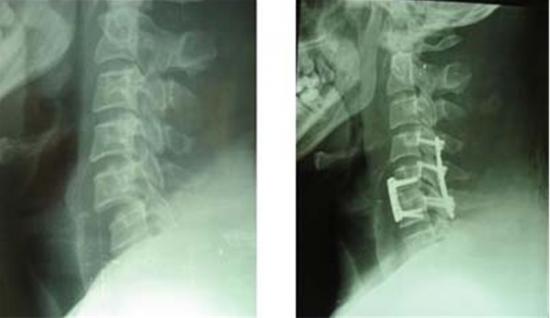

脊髓损伤(spinal cord injury)是指由于外界直接或间接因素导致脊髓损伤,在损害的相应节段出现各种运动、感觉和括约肌功能障碍,肌张力异常及病理反射等的相应改变。脊髓损伤的程度和临床表现取决于原发性损伤的部位和性质。在中医学属外伤瘀血所致“腰痛”、“痿证”、“癃闭”等病证范畴。脊髓损伤可分为原发性脊髓损伤与继发性脊髓损伤。前者是指外力直接或间接作用于脊髓所造成的损伤。后者是指外力所造成的脊髓水肿、椎管内小血管出血形成血肿、压缩性骨折以及破碎的椎间盘组织等形成脊髓压迫所造成的脊髓的进一步损害。

一般情况下,脊髓损伤多由外伤引起,交通事故、体育事故、高空作业事故、矿井事故等均可导致脊髓损伤,尤其是头部受撞击引起颈椎损伤,或背部砸伤、坠落时臀部落地伤引起胸腰段脊椎骨折,诱发脊髓损伤。比如跳水时,水浅,头部着地引起颈椎脱位、脊髓损伤,又如矿井中,煤块砸伤腰部,引起胸腰段脊椎骨折脱位,均可引起脊髓损伤。